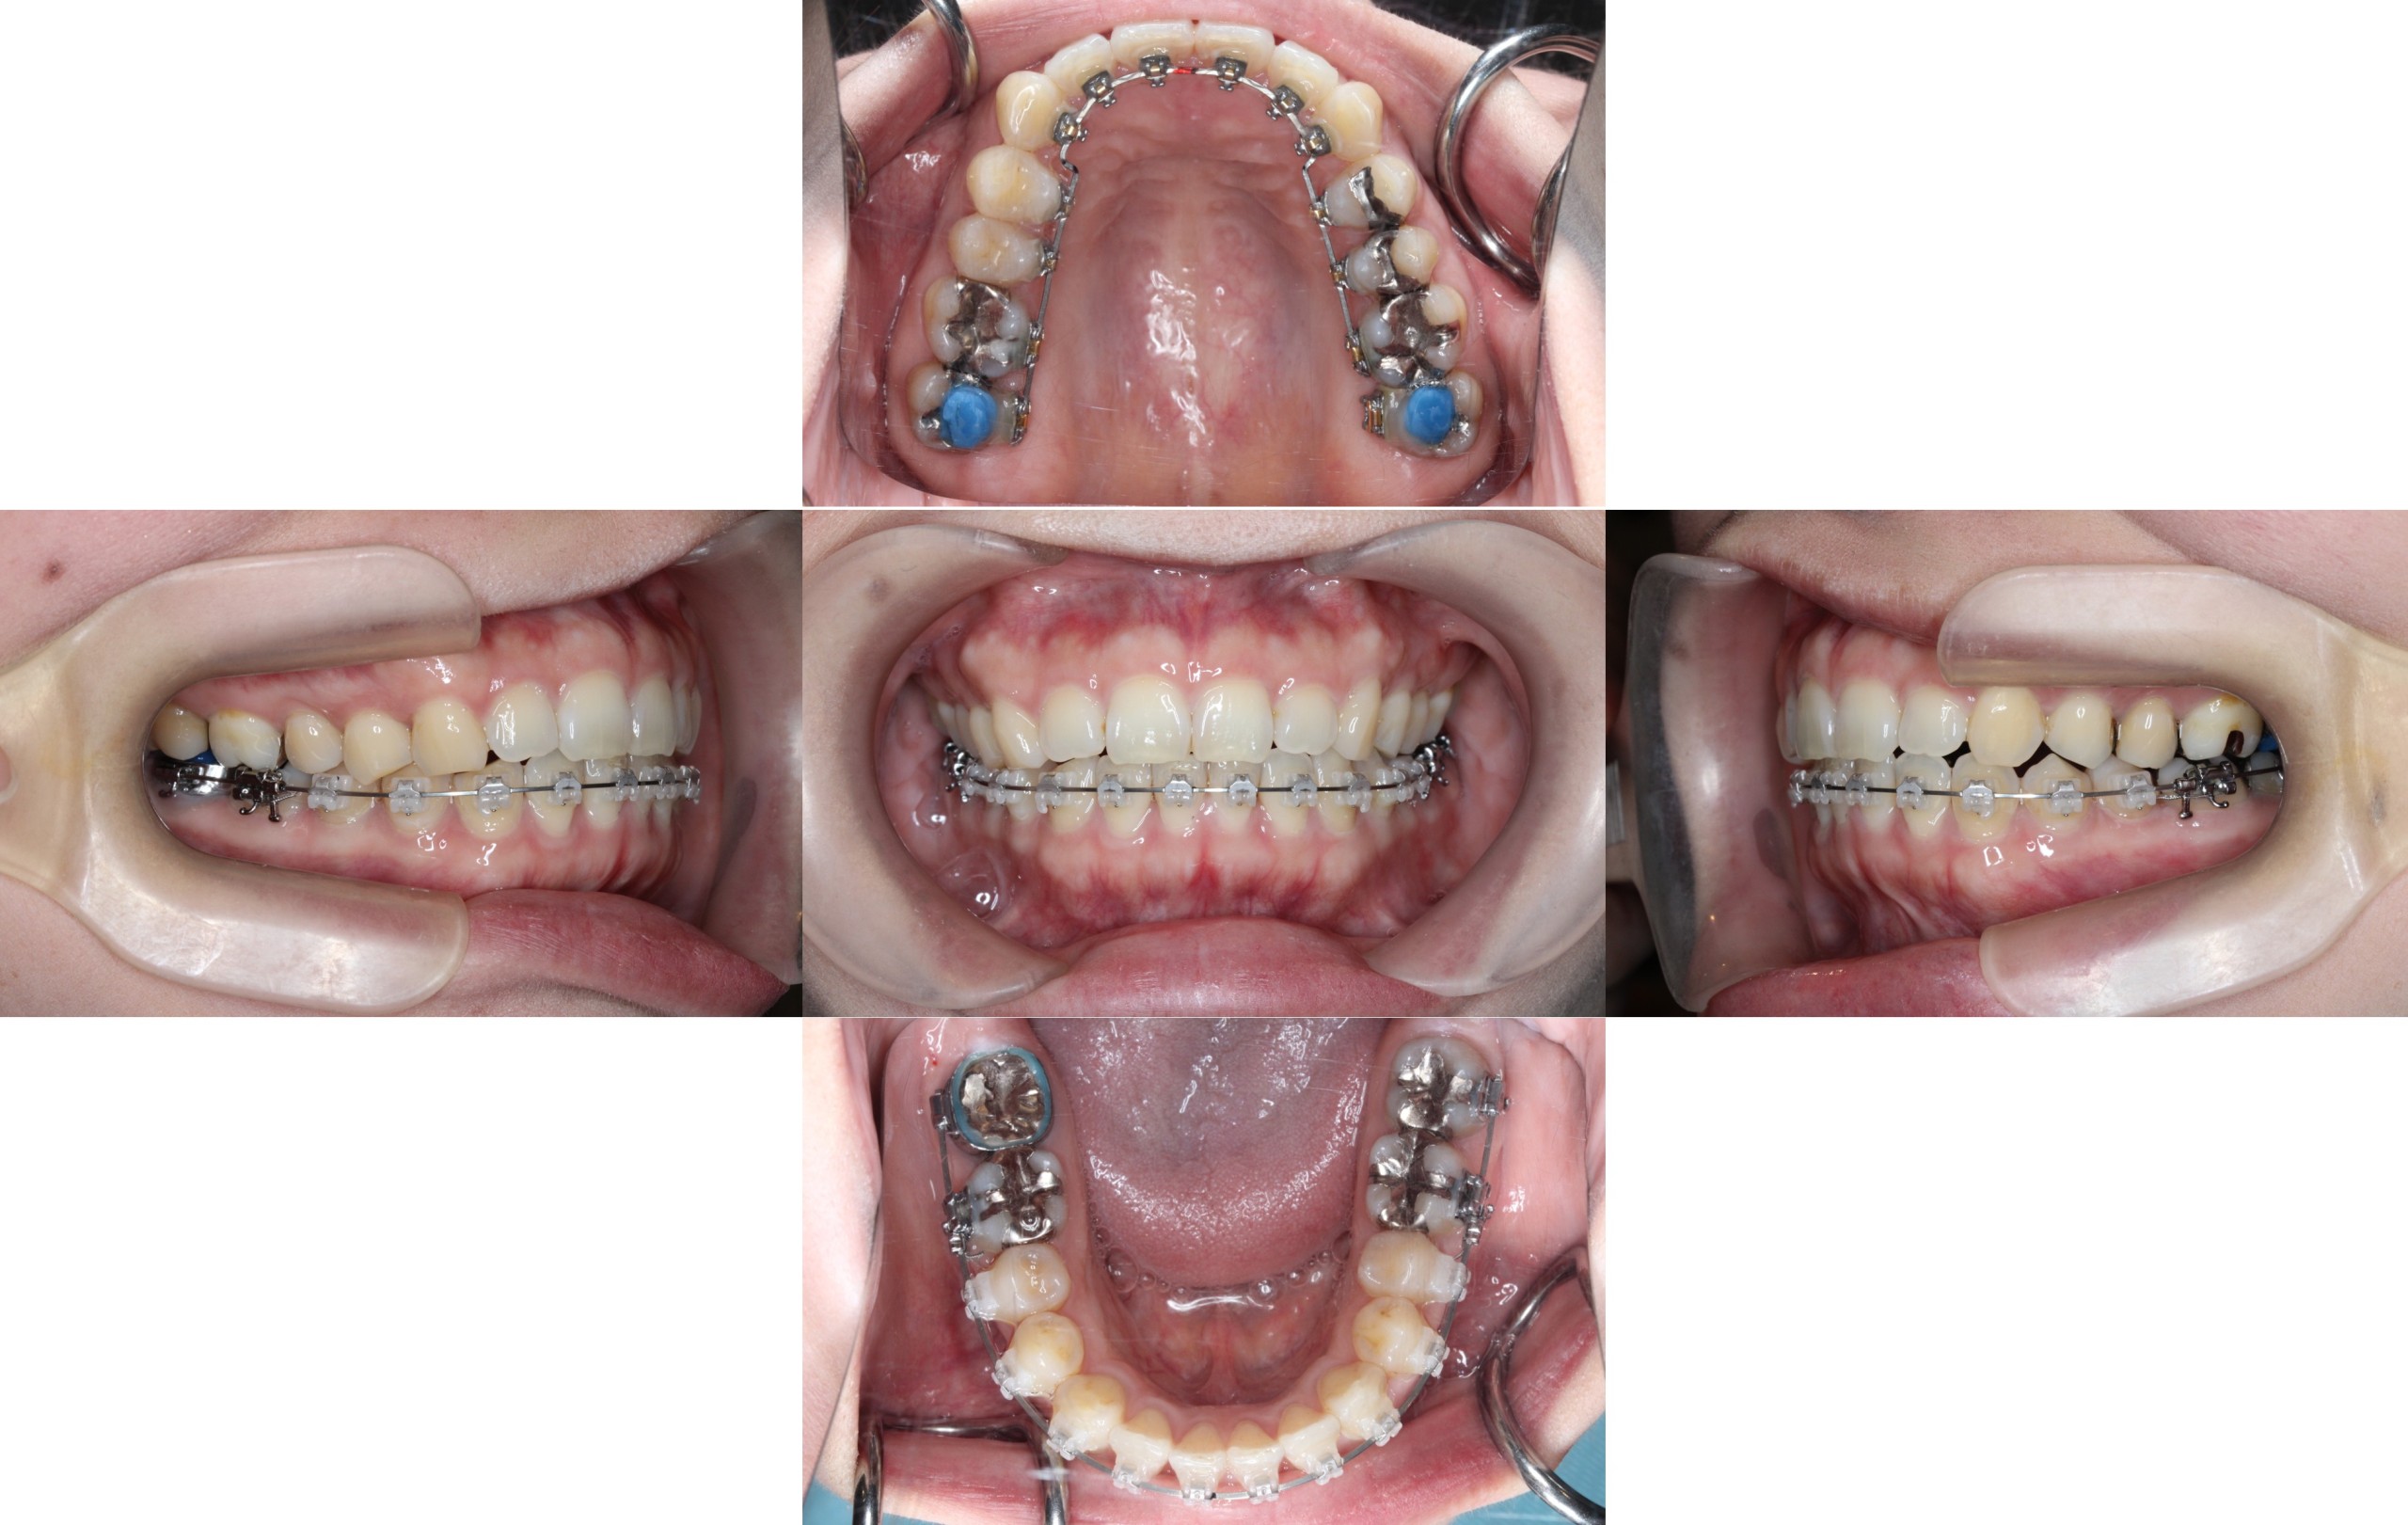

Before

初診